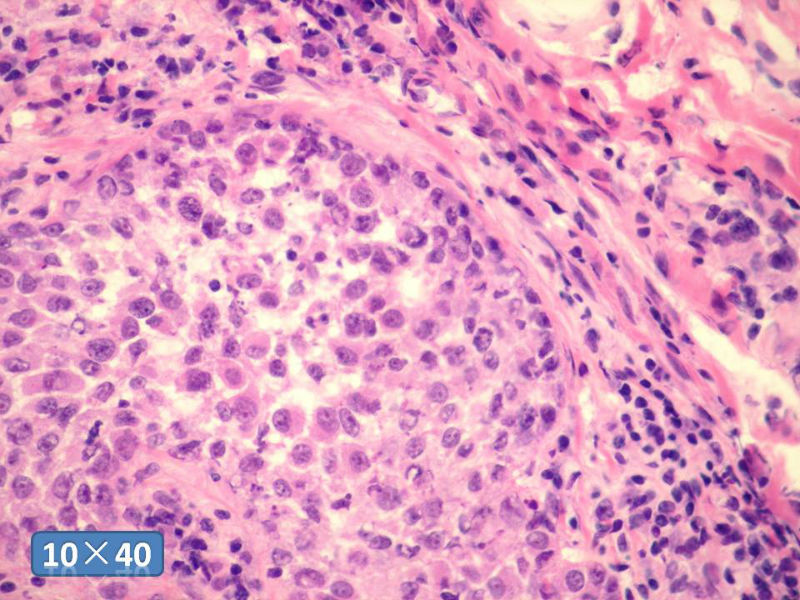

女性,50岁,乳腺肿物,冰冻切片(图1-25)

HE